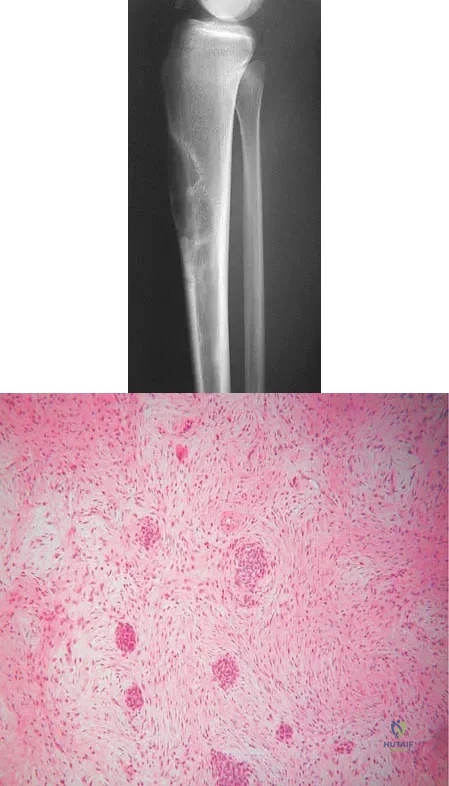

A 16-year-old girl has had anterior leg pain and a mass for the past 8 months. Figures 2a and 2b show a radiograph and an H & E histologic specimen. Which of the following disorders is believed to be a precursor of this lesion?

Explanation